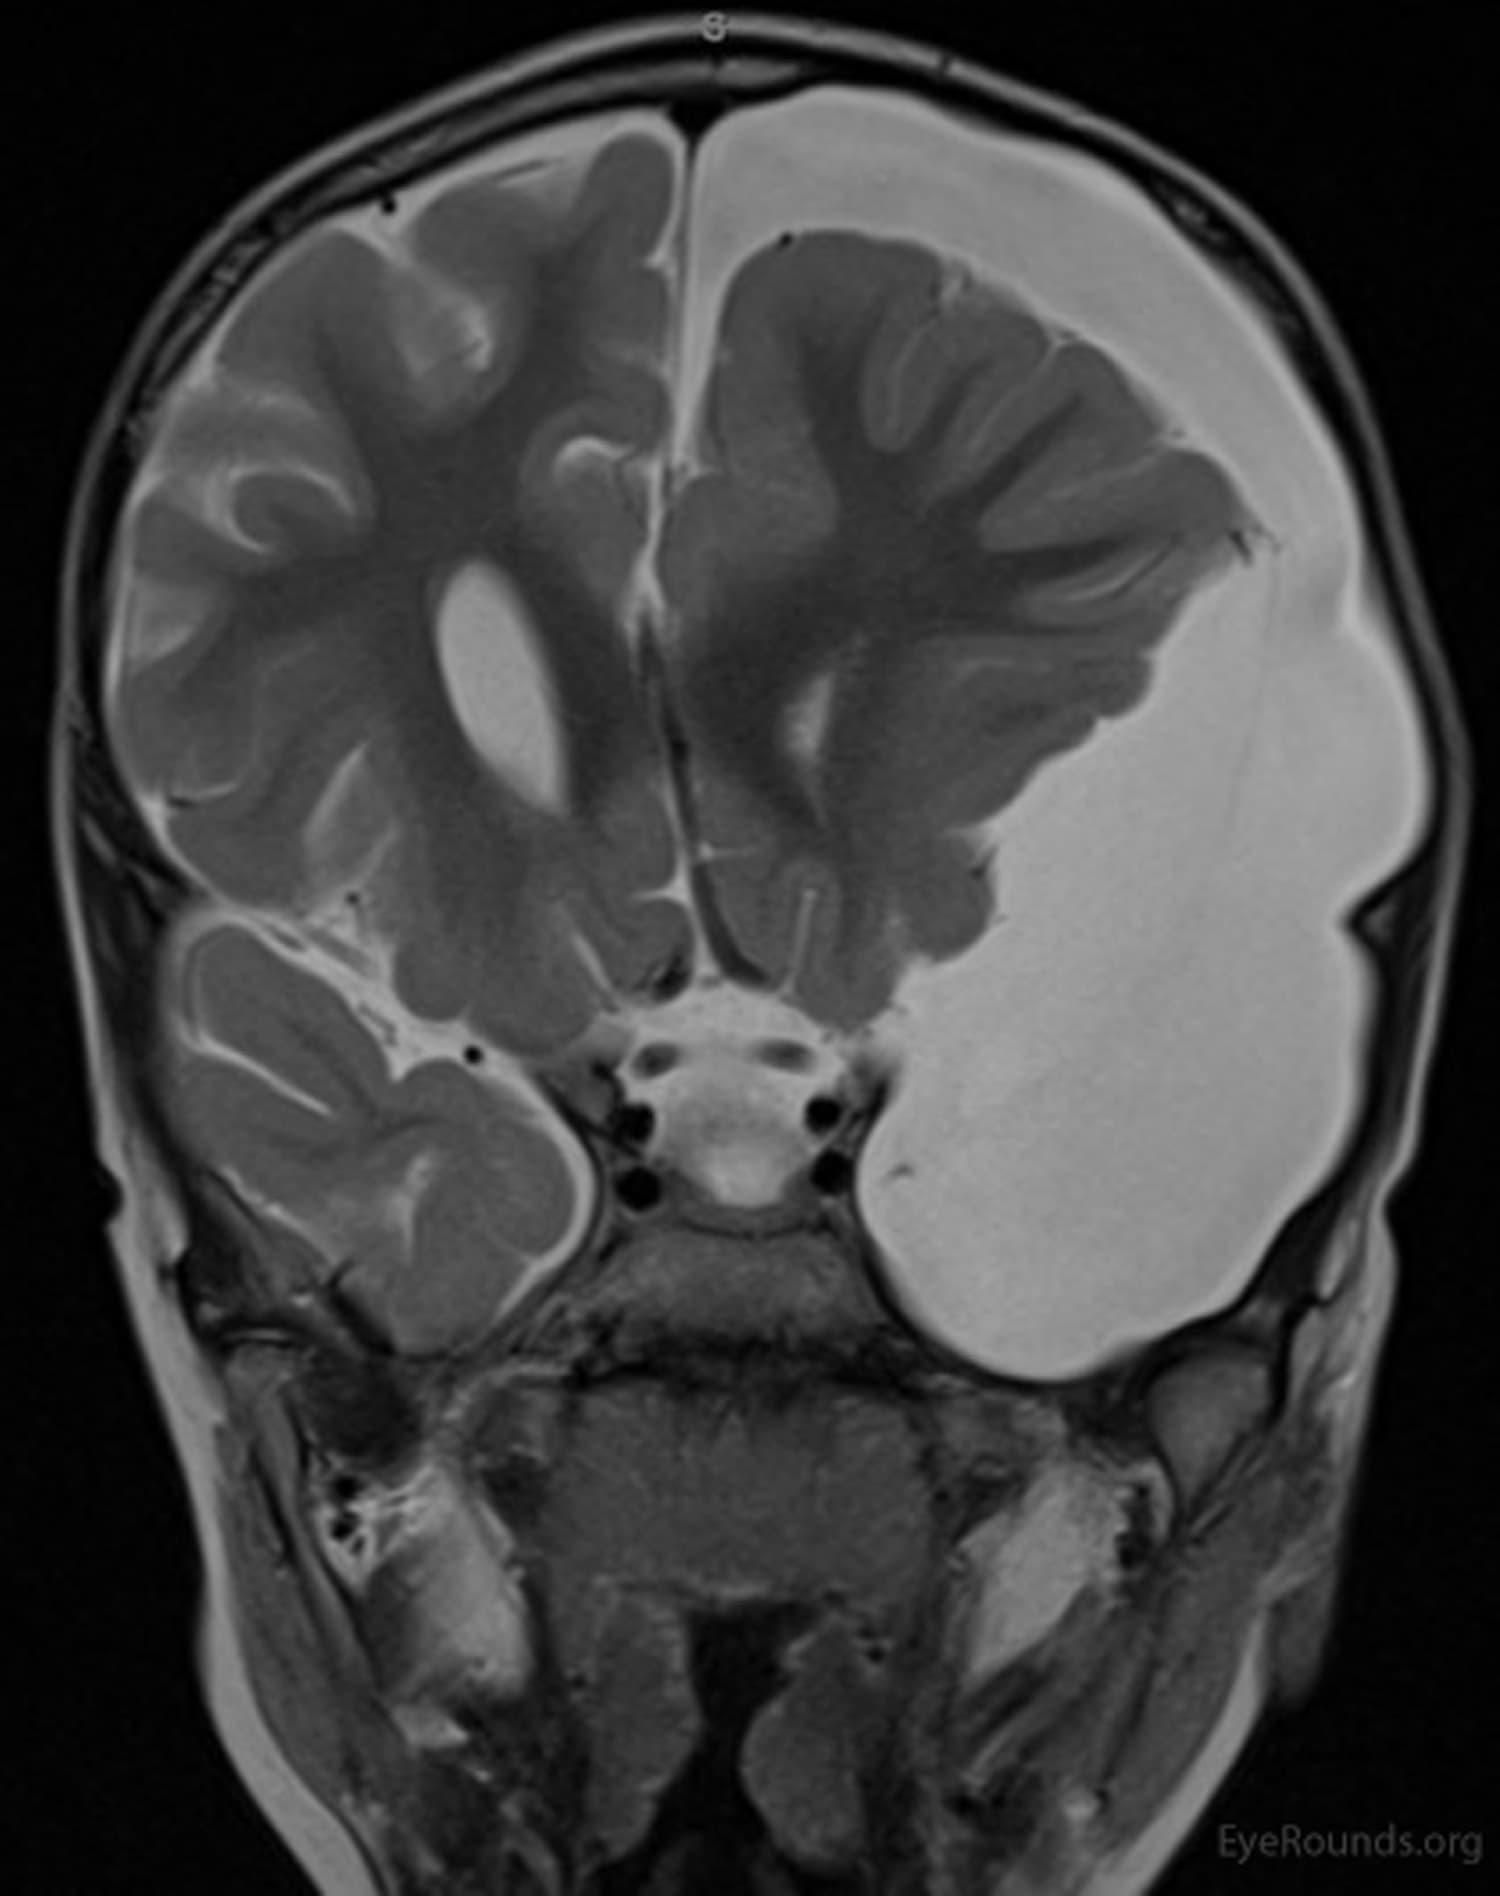

Clinical Images

High-resolution clinical photographs showing various presentations of cranial nerve palsies (cn 3, 4, 6).